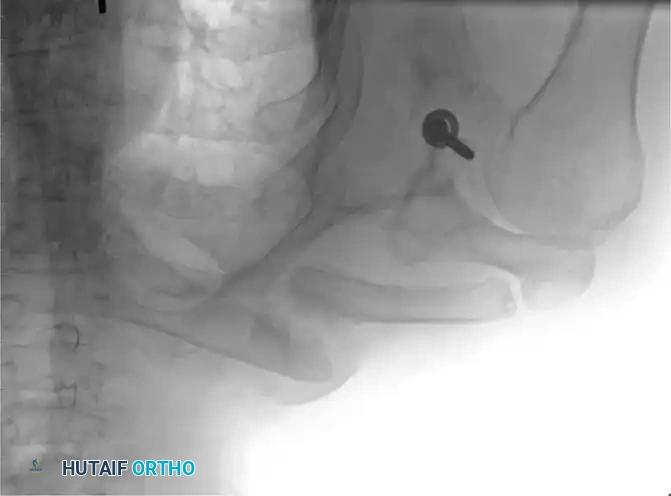

Fig. 55-26A: Midshaft clavicular malunion with significant shortening and inferior displacement.

If the clinical shortening is substantially greater than the observed radiographic shortening, an intercalary structural bone graft (autograft from the iliac crest or allograft) will be required to compensate for the absolute bone loss and restore the native shoulder span.

Associated Surgical & Radiographic Imaging